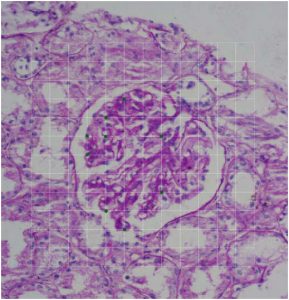

Previous PostPrevious Significance of Glomerular PAS Positive Matrix Deposition in Glomerulonephritis